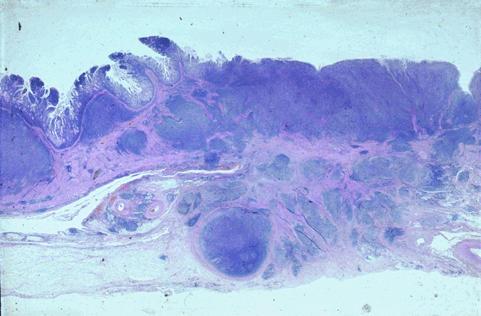

浸润小肠壁全层的恶性淋巴瘤的周围伴有弥漫性微小淋巴性息肉病一例

恶性淋巴系肿瘤/恶性淋巴瘤

小肠/空肠

病理切片(微观)

40以上

s(a)

有(同时性)